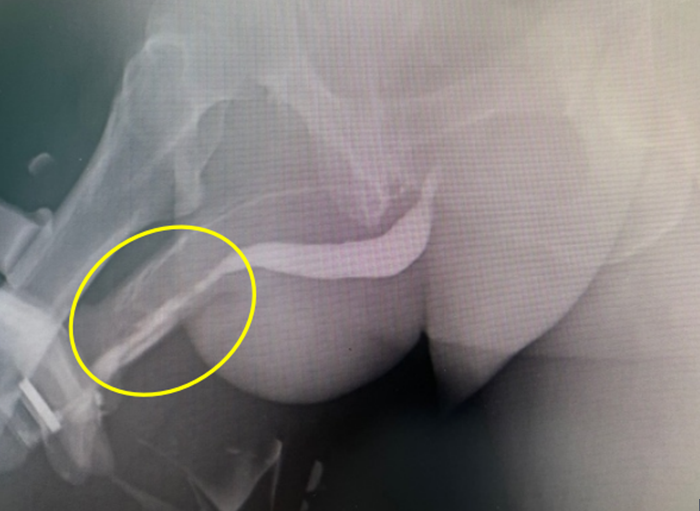

经过详细了解病史及进行体格检查后,中山七院泌尿外科廖国龙副主任医师怀疑丁先生可能患有尿道狭窄。随后,通过尿道造影检查,发现丁先生的前尿道确实存在狭窄段,而且长达近6cm。

术前尿道造影提示前尿道狭窄6cm